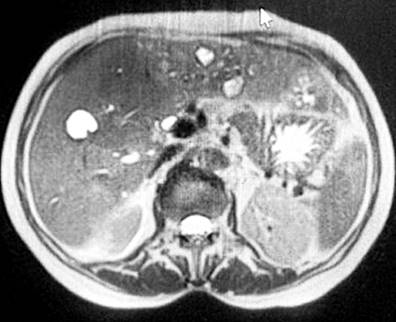

In the last five years, she was evaluated in different health centers, reporting laboratory studies, digestive screening (universal erythematous gastropathy, with Helicobacter pylori +), and colonoscopy without pathological findings. In addition, an abdominal resonance was performed, obtaining axial and coronal planes in T2, T1, T2FAT-SAT, FASE, and FS images, with and without contrast medium. They showed an enlarged liver and preserved morphology, with multiple cystic lesions randomly distributed in both liver lobes and an annular enhancement of the contrast medium (Figure 1). Magnetic resonance cholangiography was also performed, which revealed significant dilation of the intrahepatic bile duct, specifically the left one, and a well-defined cystic lesion with regular borders, which caused dilation of the extrahepatic bile duct (Figure 2). After injection of the contrast medium, a filling defect was observed, suggesting choledocholithiasis in the left hepatic duct. A biopsy was performed that did not report findings suggestive of malignancy, so we decided to manage the acute clinical picture with antibiotic therapy (carbapenems) only and periodic follow-up of the lesion.

Figure 1 Abdominal resonance of axial and coronal planes. Liver measuring 22 cm in the longitudinal axis, regular borders, having multiple cystic lesions in both liver lobes with annular contrast enhancement. Source: Patient’s medical record.